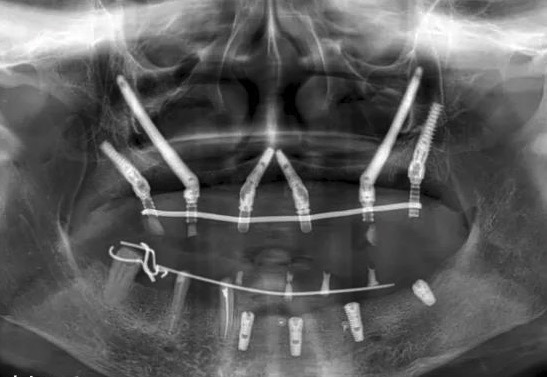

穿颧种植牙是上颌骨严重骨吸收情况下的一种有效替代治疗方法,也可被用于上颌骨缺损的修复治疗,既避免了大量的植骨手术,且能明显缩短种植治疗周期。

效果展示

手术方式

1. 骨量充足的 1 区及双侧缺骨的 2、3 区:建议 2-4 颗传统轴向种植体位于 1 区,双侧 2 或 3 区各加一颗颧骨种植体。

2. 骨量充足的 1 区及一侧缺骨的 2、3 区:建议缺骨侧 2、3 区一颗颧骨种植体,对侧 2、3 区及 1 区采用常规种植体。

3. 缺骨的 1 区及骨量充足的 2、3 区:一颗颧骨前种植体加后方常规种植体即可。

4. 1、2、3 区均缺骨:4 颗颧骨种植体即可。

项目优点

避免取骨、植骨等附加手术,而且种植当天可以短时间戴固定牙,能实现即刻负重,大大缩短了治疗时间。是上颌骨重度骨吸收情况下的一种有效替代治疗方法,也可被用于上颌骨缺损的修复治疗,既避免了大量的植骨手术,且能明显缩短种植治疗周期。